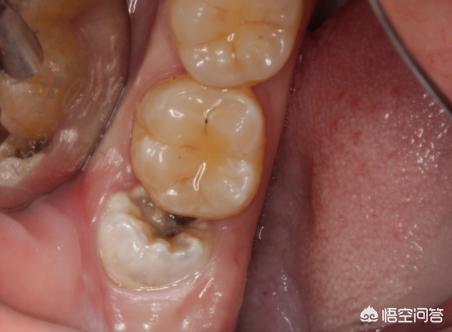

2、除了创口痛,干槽症牵引到头痛才最难受,要注意缝合伤口,减少细菌感染的风险,一周后再去拆线,可能还会有牙洞要注意清水漱口,这时的创口已经不会痛,想要避免干槽症,拔智齿最好到医院做微创拔除手术,这样出血也不会过多。

拔完智齿当然是会痛的,创口较大就得缝合,只要保护好血凝块,预防干槽症的同时,炎症也在逐渐好转。